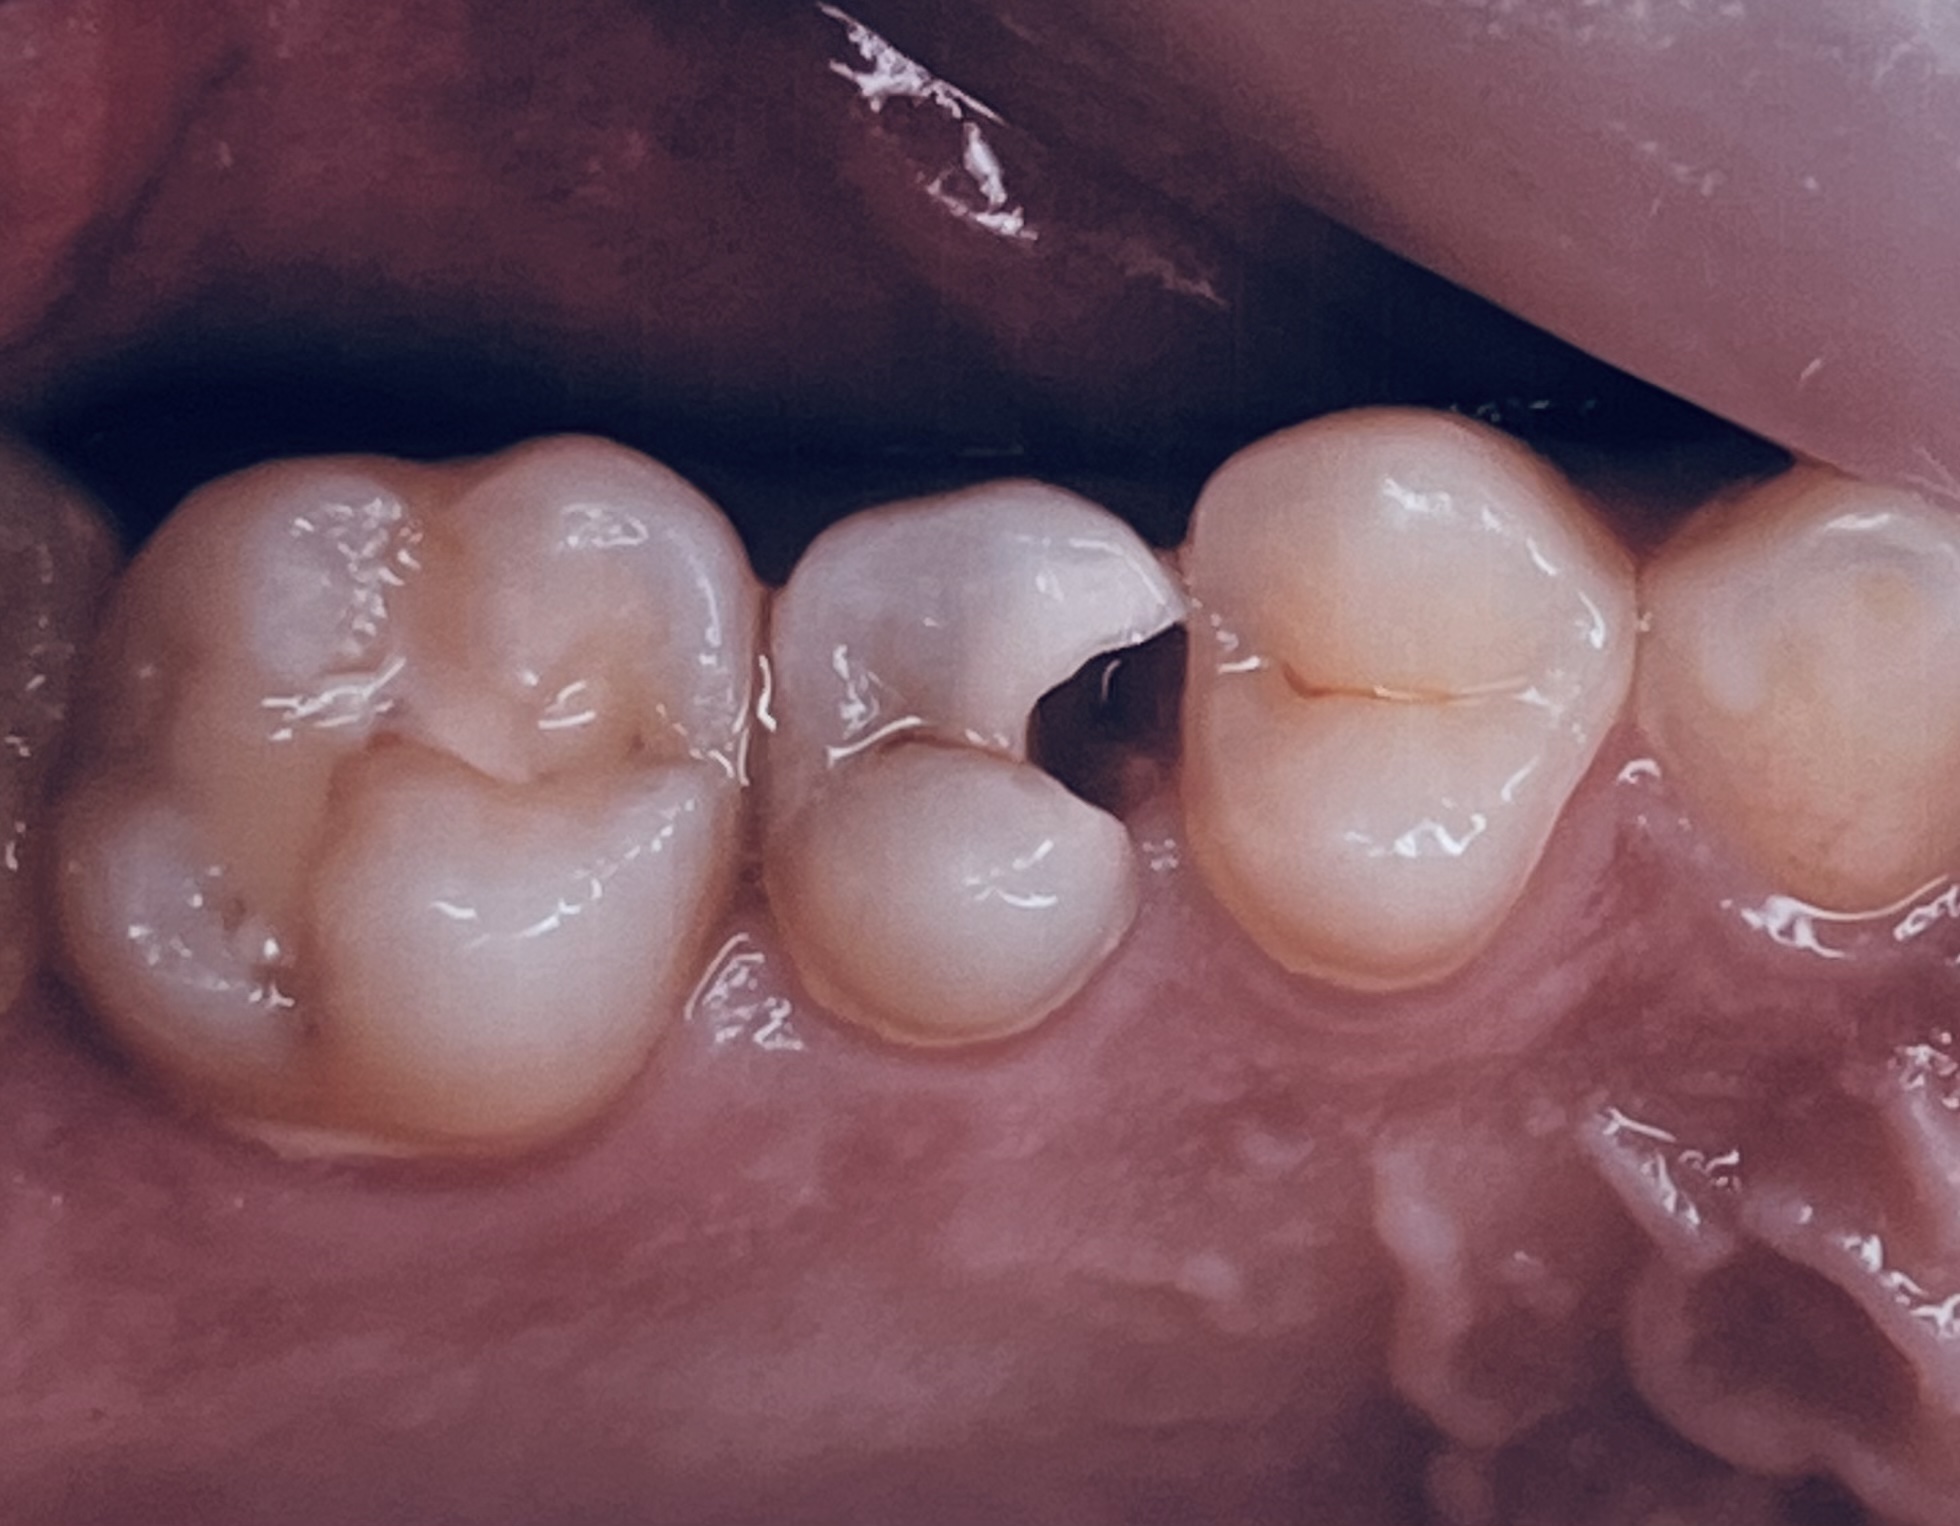

上野中おくの歯に大きな穴が開いてるのはわかると思いますが、実は中でもっと大きな虫歯が進行しておりました。患者様と相談し、残念だけれども痛みもあるし神経を取る治療をしました。

上の写真は、虫歯を治療しジルコニアセラミックが入った状態です。ほとんど隣の歯との違いがなく違和感が少ないのがわかると思います。